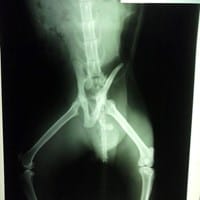

Gato fracturado con tutor externo

Se trata de un gato semi-salvaje que fue atropellado hace 10 días y sufrió fractura de cadera. Se le realizó cirugía y colocó un tutor externo. Sé que el reposo es fundamental (por lo cual lo tengo en una jaula/canil de internación de las que usan en...